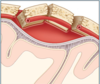

Q

What type of haemorrhage is this?

A

Subdural